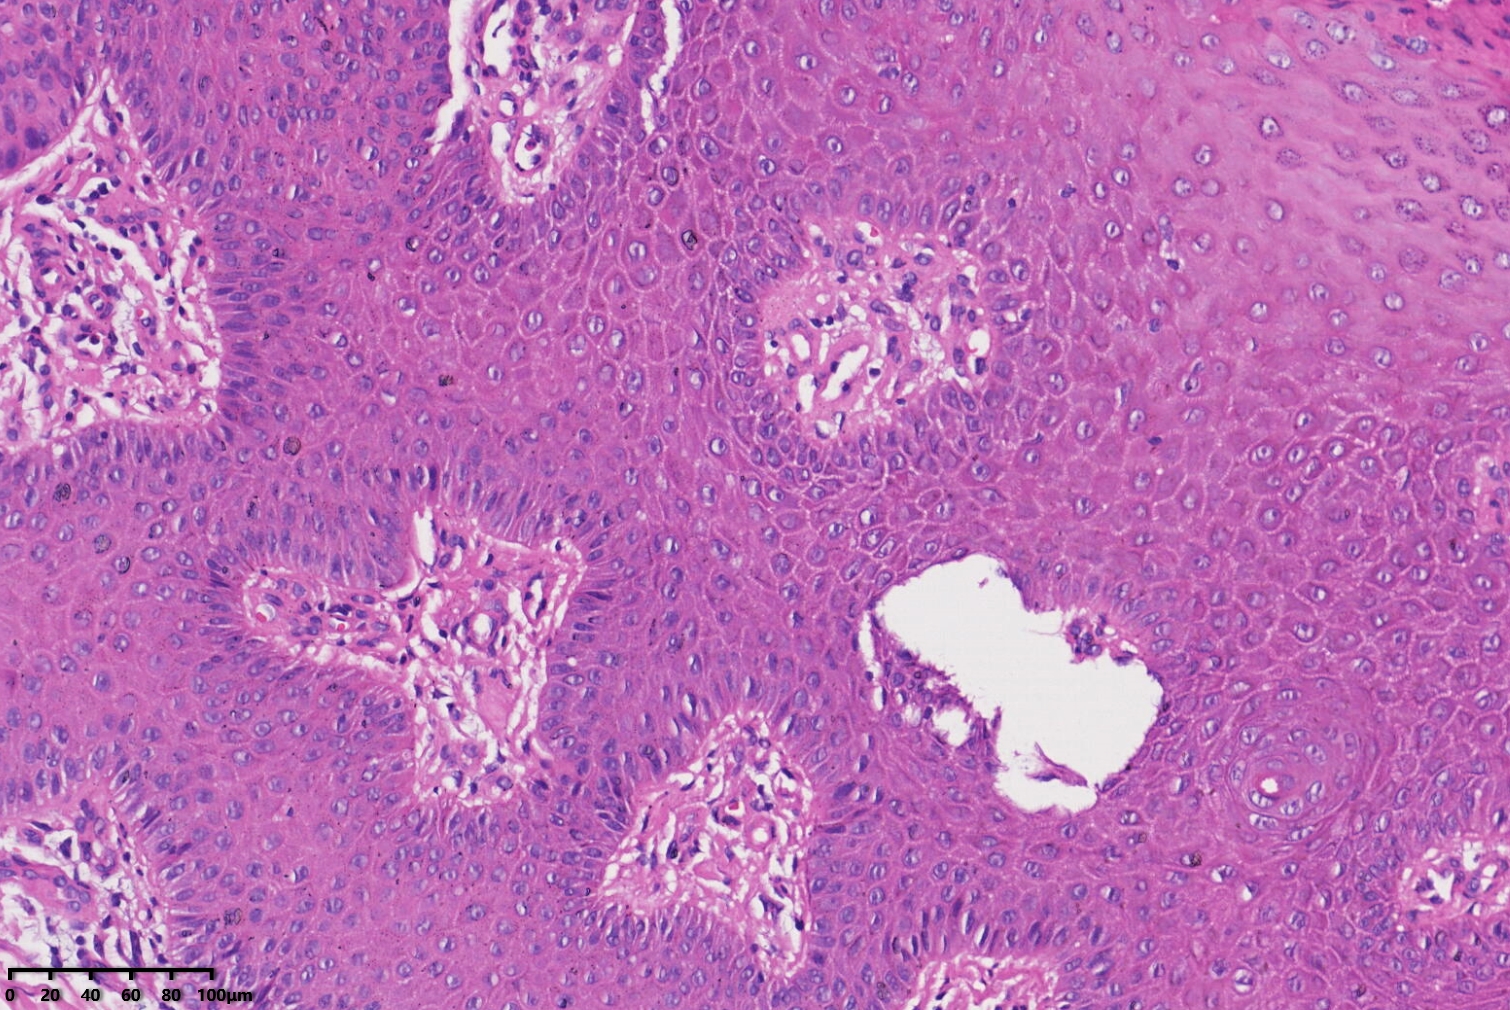

汗孔瘤?

性别

女

年龄

53岁

左足部皮肤包块

汗孔瘤。

脂溢性角化病